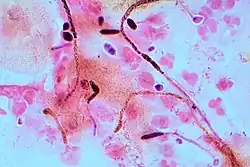

A United States study in 2022 showed that most cases of candidiasis are treated empirically (without culture, pending culture or by symptoms in cases where culture did not show candida), thus not knowing whether the subtype is Candida albicans or any other candida species.[94] For subtyping of candidiasis, a fungal culture can be performed, followed by a germ tube test in which a sample of fungal spores are suspended in animal serum and examined by microscopy for the detection of any germ tubes.[95] Colonies of white or cream color on fungal culture having a positive germ tube test is strongly indicative of Candida albicans.[95]

Germ tubes of Candida albicans

Germ tubes of Candida albicans -

Gram stain of Candida albicans from a vaginal swab; the small oval chlamydospores are 2–4 μm in diameter

Gram stain of Candida albicans from a vaginal swab; the small oval chlamydospores are 2–4 μm in diameter -